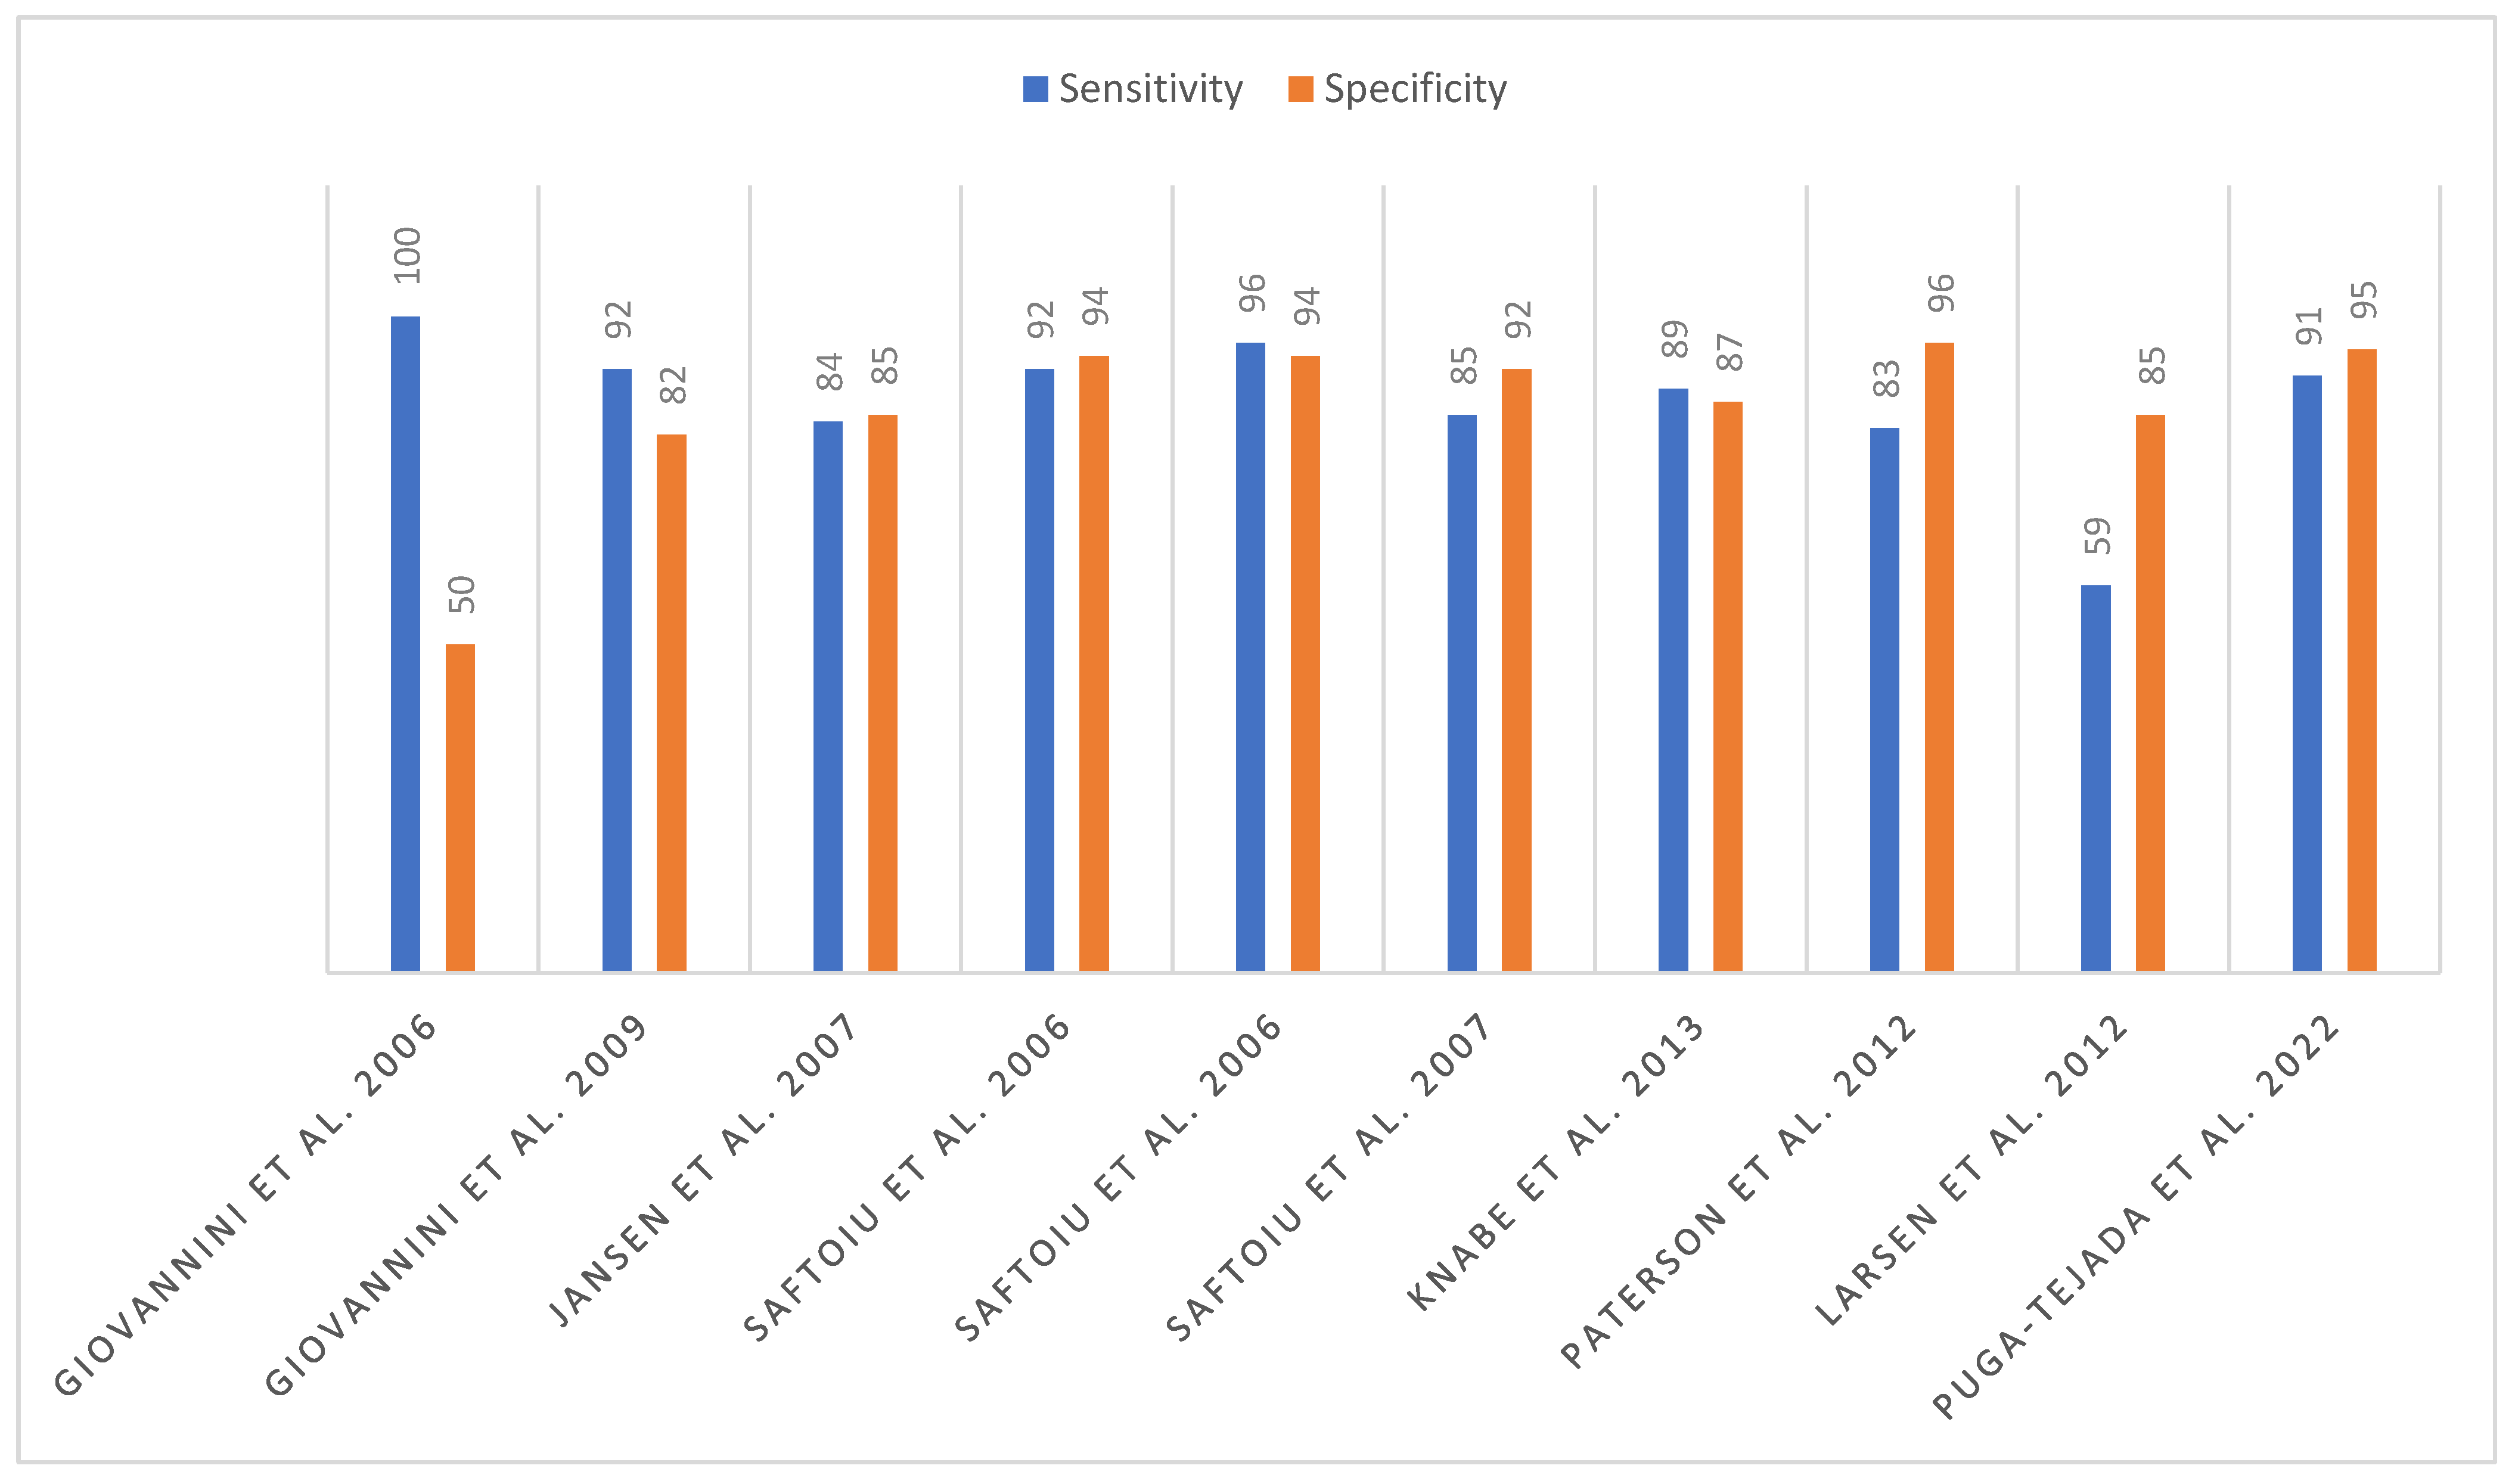

5. Lymph Nodes

- Dietrich, C.F.; Jenssen, C.; Arcidiacono, P.G.; Cui, X.W.; Giovannini, M.; Hocke, M.; Iglesias-Garcia, J.; Saftoiu, A.; Sun, S.; Chiorean, L. Endoscopic ultrasound: Elastographic lymph node evaluation. Endosc. Ultrasound 2015, 4, 176–190. [Google Scholar] [CrossRef]

- Janssen, J.; Dietrich, C.F.; Will, U.; Greiner, L. Endosonographic elastography in the diagnosis of mediastinal lymph nodes. Endoscopy 2007, 39, 952–957. [Google Scholar] [CrossRef]

- Săftoiu, A.; Vilmann, P.; Ciurea, T.; Popescu, G.L.; Iordache, A.; Hassan, H.; Gorunescu, F.; Iordache, S. Dynamic analysis of EUS used for the differentiation of benign and malignant lymph nodes. Gastrointest. Endosc. 2007, 66, 291–300. [Google Scholar] [CrossRef]

- Paterson, S.; Duthie, F.; Stanley, A.J. Endoscopic ultrasound-guided elastography in the nodal staging of oesophageal cancer. World J. Gastroenterol. 2012, 18, 889–895. [Google Scholar] [CrossRef]

- Larsen, M.H.; Fristrup, C.; Hansen, T.P.; Hovendal, C.P.; Mortensen, M.B. Endoscopic ultrasound, endoscopic sonoelastography, and strain ratio evaluation of lymph nodes with histology as gold standard. Endoscopy 2012, 44, 759–766. [Google Scholar] [CrossRef]

- Săftoiu, A.; Vilmann, P.; Hassan, H.; Gorunescu, F. Analysis of endoscopic ultrasound elastography used for characterisation and differentiation of benign and malignant lymph nodes. Ultraschall Med. 2006, 27, 535–542. [Google Scholar] [CrossRef]

- Knabe, M.; Günter, E.; Ell, C.; Pech, O. Can EUS elastography improve lymph node staging in esophageal cancer? Surg. Endosc. 2013, 27, 1196–1202. [Google Scholar] [CrossRef]

- Xu, W.; Shi, J.; Zeng, X.; Li, X.; Xie, W.F.; Guo, J.; Lin, Y. EUS elastography for the differentiation of benign and malignant lymph nodes: A meta-analysis. Gastrointest. Endosc. 2011, 74, 1001–1009. [Google Scholar] [CrossRef] [PubMed]